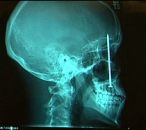

We think we've found the cause of your toothache.

LITTLETON, Colo. — A dentist found the source of the toothache Patrick Lawler was complaining about on the roof of his mouth: a 4-inch nail the construction worker had unknowingly embedded in his skull six days earlier...

"This is the second one we've seen in this hospital where the person was injured by the nail gun and didn't actually realize the nail had been imbedded in their skull," neurosurgeon Sean Markey told KUSA-TV in Denver...

"The doctors said, 'If you're going to have a nail in the brain, that's the way you want it to be.'..." [AP]